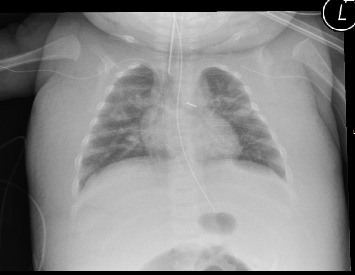

There are several causes of generalized edema in sick neonates. We describe two newborns that developed progressive and treatment-resistant generalized edema. We suggest this is due to impaired lymphatic flow from the thoracic duct as a result of a central venous catheter in the left subclavian vein.